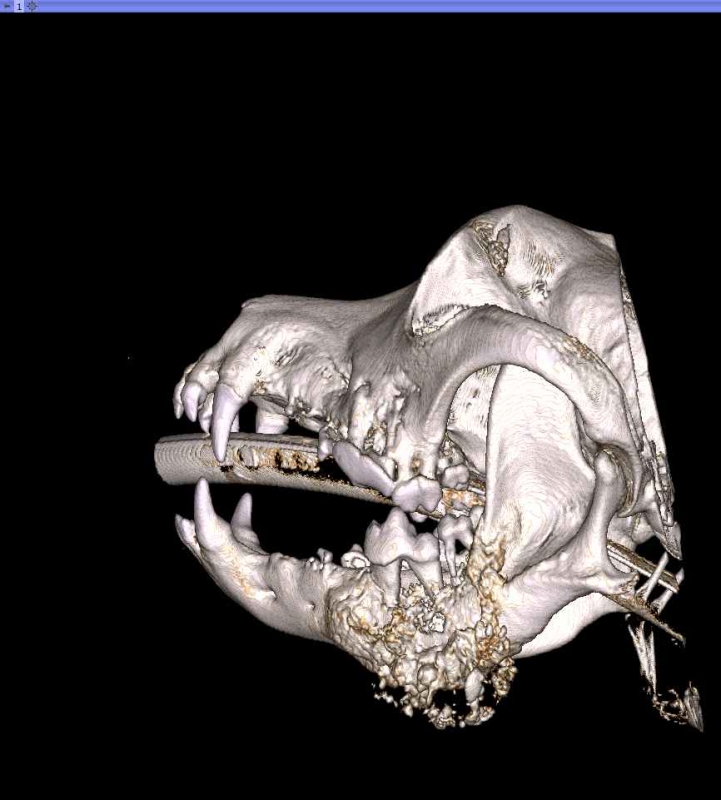

Cone Beam Computed Tomography

The Center now provides advanced imaging via cone beam CT. Cone beam CT is excellent for visualization of bony structures of the skull, nasal cavity, teeth, and ears. Cone beam CT is especially helpful for diagnosing dental disease and evaluation of jaw fractures. It can also be useful for evaluating the sinuses and tympanic bulla. Cone beam CT can be used in conjunction with nasal biopsy and culture to evaluate nasal discharge whether chronic or acute.

Repair of Maxillofacial Fracture

Pets can be involved in trauma that can cause fractures to their head, teeth, and jaw bones. Correctly repairing these fractures is extremely important for your pet to have normal function of their mouth. If a jaw fracture is allowed to heal in an abnormal position, your pet may have great difficulty chewing and can be in significant pain. Many fractures can be successfully treated with minimally invasive oral procedures, but more complicated cases may require bone plating techniques. The Center offers cone beam CT imaging which provides extremely detailed images of the bones of the head and skull. Advanced imaging with CBCT facilitates selection of the best surgical technique to get your pet back to eating and comfort as soon as possible.